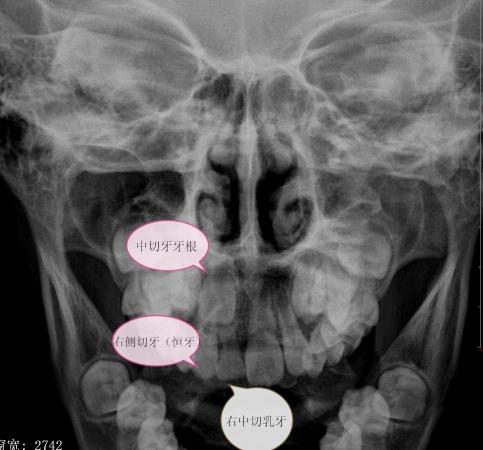

男,9岁10个月,右侧中切牙乳牙未换,右侧切牙已换。牙片显示右中切牙恒牙位置异常,与右侧切牙(恒牙)部分重叠,且右中切牙恒牙牙根稍短小(位置影响?),如何处理?能否矫正?